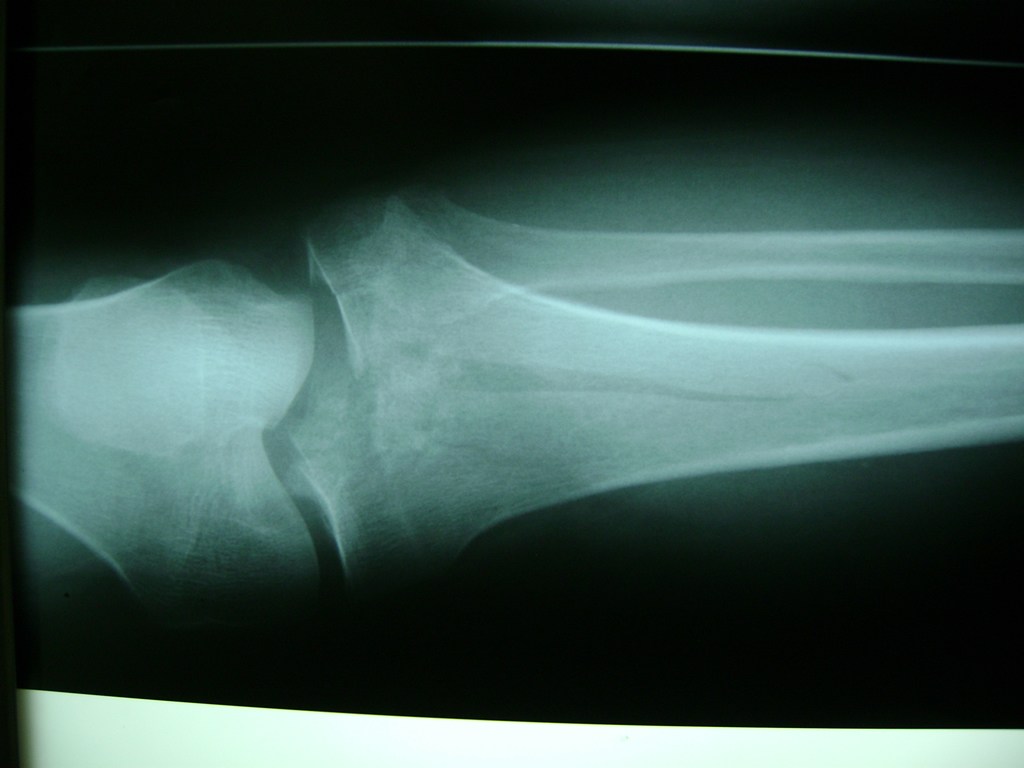

Cirugías de Tobillos